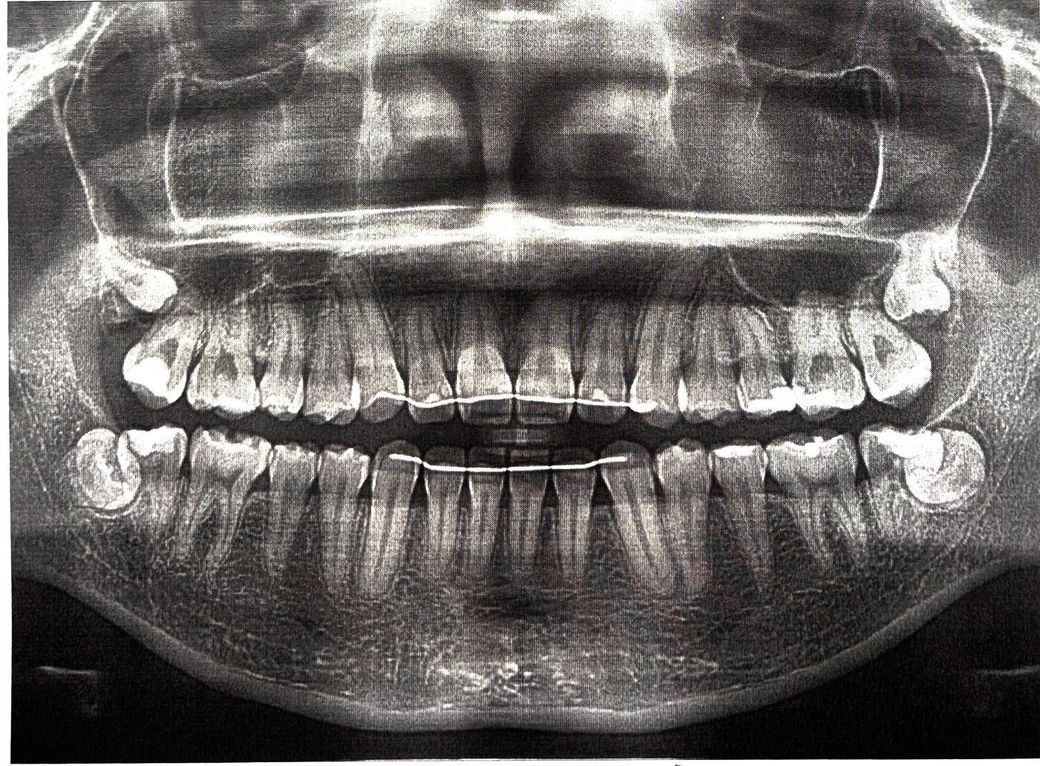

엑스레이 상으로는 충치가 잇어 보이진 않습니다. 착색이 된게 아닐까 생각되니 관리만 잘해주시면될것같습니다 .

셀카모드로 좌우변경된게 아니라면 임상사진은 오른쪽 위어금니이고 방사선사진상에서는 약간 썩어보이는 듯 하지만 이 둘 가지고는 사실 무조건 충치다 아니다 판별할 수 없습니다. 조그만 Periapical radiograph를 찍어봐야 알 수 있습니다.

현재 충치일 가능성이 높아보이며, 보다 정확한 확인 및 초기에 치료를 위해 바로 치과 진료를 받아보길 권합니다.